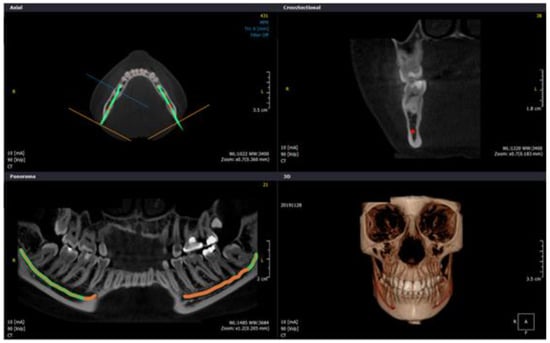

2.4. Study Protocol and Image Analysis

- I.

- Buccalcortical plate to IAN dimension (BCPN): Linear distance from the IAN to the nearest corresponding buccal outer cortical plate.

- II.

- Lingual cortical plate to IAN dimension (LCPN): Linear distance from the IAN to the nearest corresponding lingual outer cortical plate.

- III.

- Alveolar crest to IAN dimension (ACN): Linear distance from the IAN coronally to the midpoint of alveolar crest bone corresponding to the long axis of tooth.